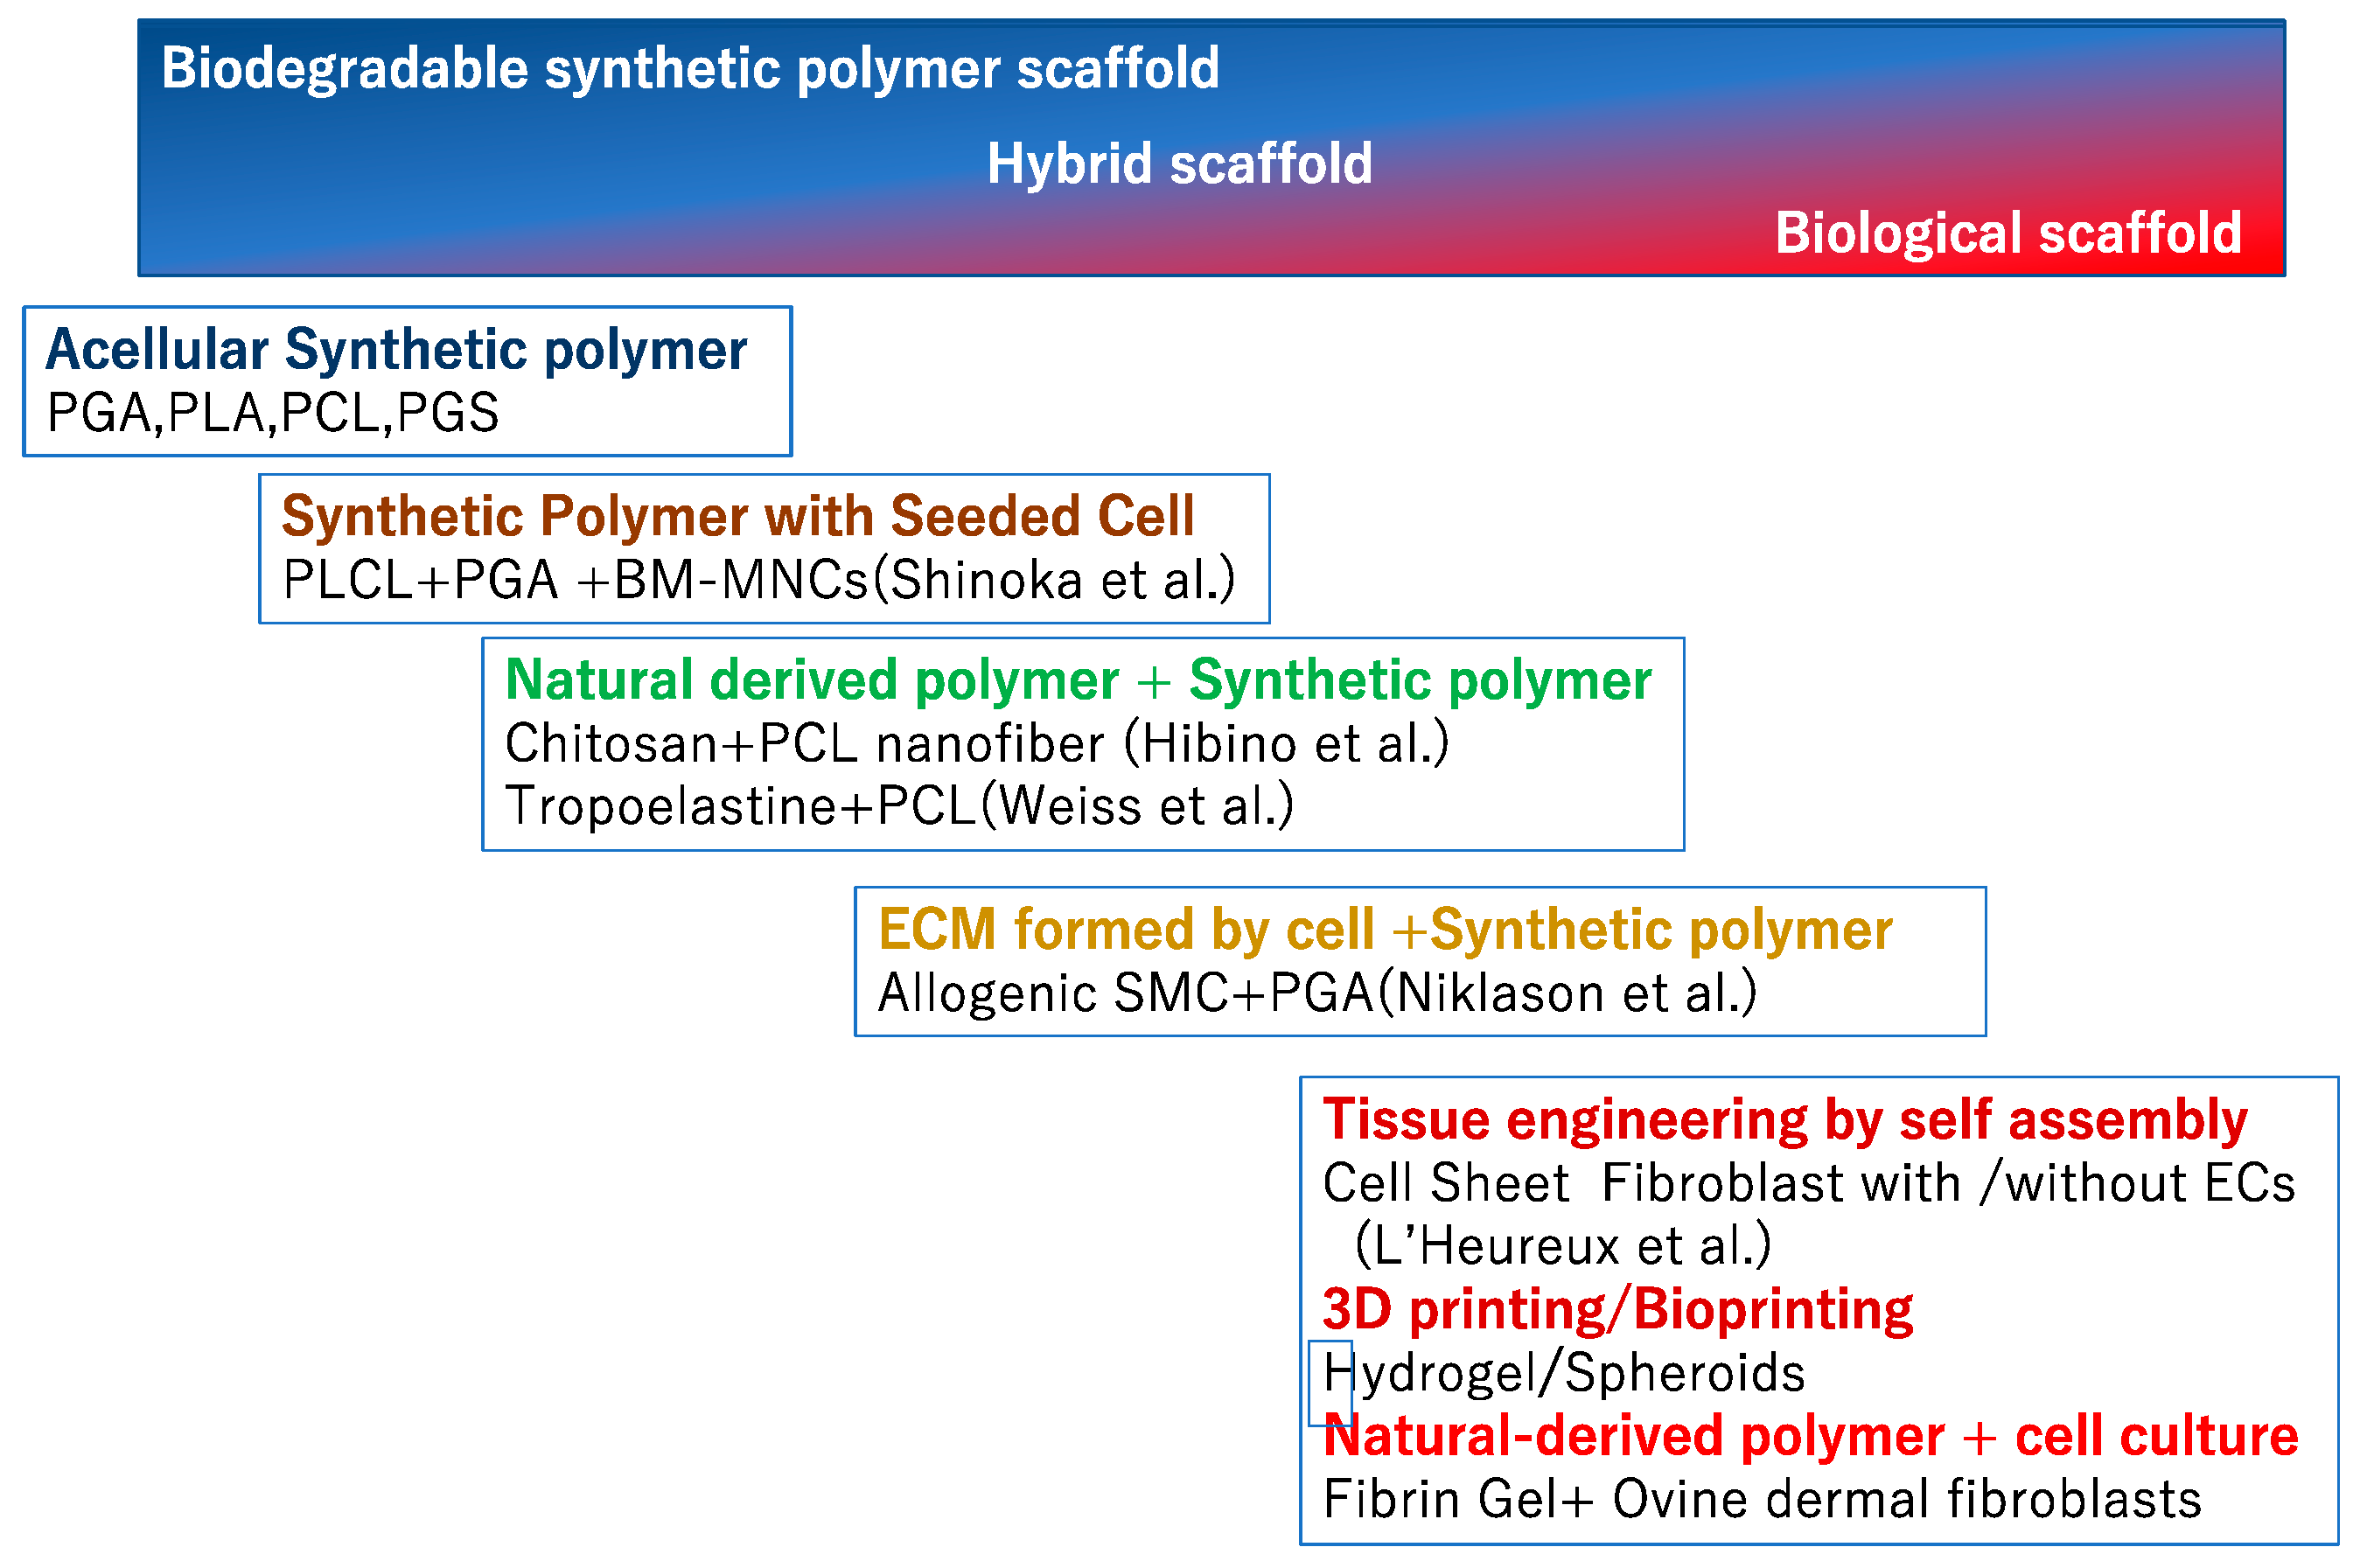

2.1. Biodegradable Synthetic Vascular Grafts

2.3. Application of Cell Biology to TEVG

3. Clinical Study in Venous Model